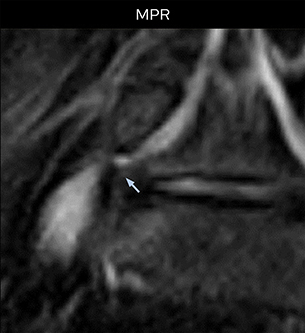

Distinguishing typical from atypical herniation informs the surgeon

“NerveVIEW is really useful for those cases where a nerve disorder is strongly suspected based on the clinical examination but our regular MRI images do not show any findings. These atypical herniations and spinal canal stenosis, occurring in 5% to 15% of the total lumbar herniation/stenosis cases are our main target when using NerveVIEW,” says Dr. Yabuki.

“Although symptoms of typical disc herniation and atypical hernia are very similar, the actual site of herniation is different. It is therefore important to characterize the nerve’s condition both inside and outside of the intervertebral foramina.